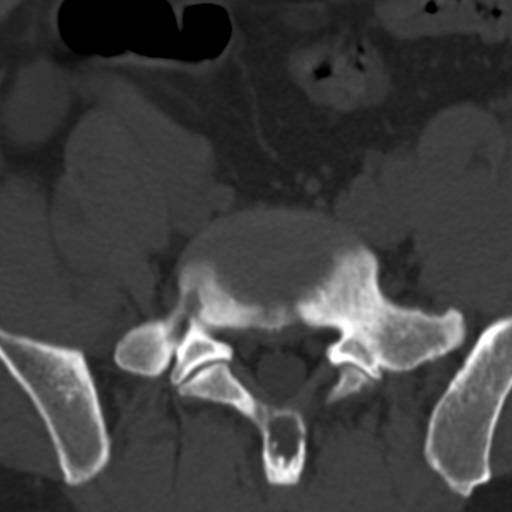

标题: CT4742:椎弓病变,请各位会诊。

男性,37岁,体检发现。

椎弓棘突形态、大小正常,左右椎板及棘突交界区骨质缺损,考虑良性病变(血管瘤可能)。

椎弓棘突形态、大小正常,左右椎板及棘突交界区骨质缺损,边缘清楚,后分见两个小点状高密影,考虑良性病变[血管瘤、成骨细胞瘤,骨纤,骨囊肿]

左右椎板及棘突交界区骨质缺损,周围未见软组织肿块及肿胀,考虑良性病变(血管瘤可能)。

破坏区呈彭胀性 切有硬化缘 考虑良性占位  囊肿可能性大